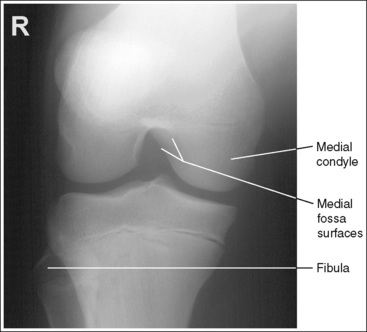

The knee demonstrates an AP projection. The medial and lateral femoral epicondyles are in profile, the femoral condyles are symmetrical, the intercondylar eminence is centered within the intercondylar fossa, and the tibia is superimposed over 0.25 inch (0.6 cm) of the fibular head.

• To obtain an AP knee projection, place the patient in a supine position with the knee fully extended. Internally rotate the leg until an imaginary line drawn between the medial and lateral femoral epicondyles is positioned parallel with the IR (Figure 6-71). This positioning places the medial and lateral femoral epicondyles at equal distances from the IR as well as medially and laterally in profile, respectively. It also centers the intercondylar eminence within the intercondylar fossa and draws the fibular neck and a portion of the fibular head from beneath the tibia.

• Effect of rotation. If the femoral epicondyles are not positioned parallel with the IR, an AP projection has not been obtained. If the patient's leg was not internally rotated enough to place the epicondyles at equal distances from the IR, they are not in profile, the medial femoral condyle appears larger than the lateral condyle, and the tibia is superimposed over more than 0.25 inch (0.6 cm) of the fibular head (see Image 54). If the patient's leg was internally rotated more than needed to place the femoral epicondyles at equal distances from the IR, the epicondyles are not demonstrated in profile, the lateral femoral condyle appears larger than the medial condyle, and the tibia is superimposed over less than 0.25 inch (0.6 cm) of the fibular head (see Image 55).

• Center the central ray to the midline of the knee at a level 1 inch (2.5 cm) distal to the palpable medial epicondyle to place the knee joint in the center of the exposure field. (As long as the knee remains extended, an alternative central ray placement is 0.5 inch (1.25 cm) distal to the patellar apex.) Open the longitudinal collimation enough to include one fourth of the distal femur and proximal lower leg. Transverse collimation should be to within 0.5 inch (1.25 cm) of the knee skin line.